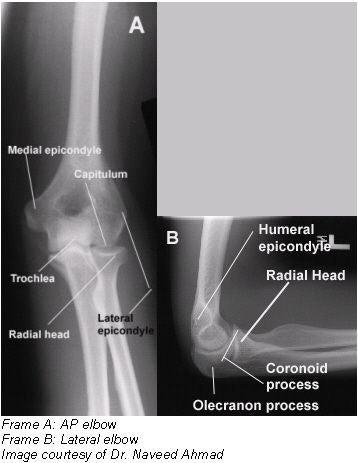

Radiographic positioning of the elbow

Routine radiographic examination of elbow is performed using the AP, AP oblique, and lateral projections. AP oblique projections include medial (internal) rotation and lateral (external) rotation views.

The lateral projection (lateromedial view) is obtained by flexing the elbow 90º. Diagnosis of certain important joint pathological processes (such as possible visualization of the posterior fat pad) depends on 90º flexion of the elbow joint. By doing this, the olecranon process can be seen in profile, and the elbow fat pads are the least compressed. Also, by allowing a partial or complete extension, the olecranon process elevates the posterior elbow fat pad and simulates joint pathology.

- Distal humerus, elbow joint space, proximal radius, and ulna should be clearly demonstrated.

- No rotation is evidenced by appearance of bilateral epicondyles seen in profile; radial head, neck, and tuberosity slightly superimposed over the proximal ulna.

- Elbow joint appears open with fully extended arm.

- Soft tissue and bony trabeculation should be visible.

- Distal humerus, proximal forearm should be clearly demonstrated.

- Open elbow joint centered to the central ray.

- Elbow flexed 90º.

- Superimposed humeral epicondyles.

- Radial tuberosity facing anteriorly.

- Radial head partially superimposing the coronoid process.

- Olecranon process seen in profile.

- A true lateral projection is indicated by three concentric arcs of the trochlear sulcus, double ridges of the capitulum and trochlea, and the trochlear notch of the ulna.

- Bony trabeculation and any elevated fat pads in the soft tissue at the anterior and posterior distal humerus and the anterior proximal forearm should be visible.